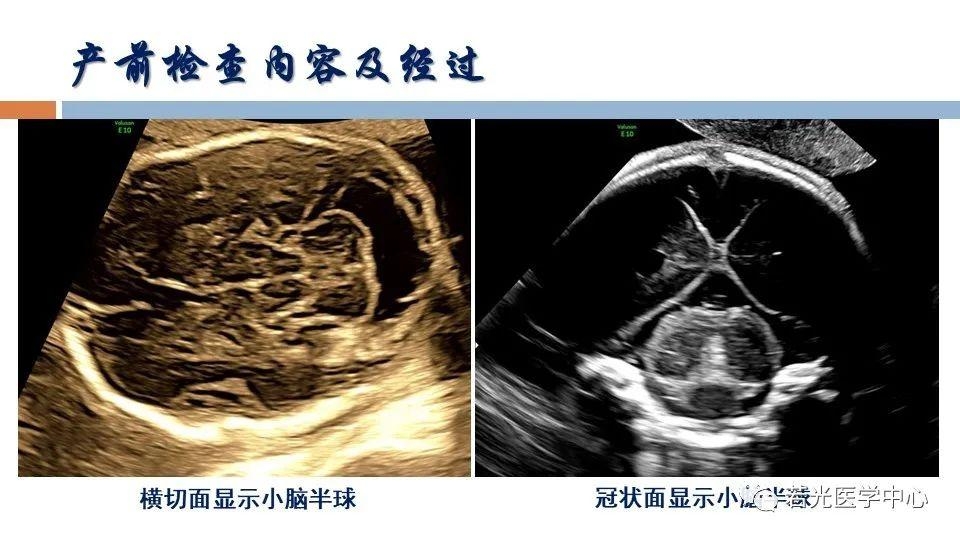

(6)表型-征象-分子遗传联合分析,遗传咨询分析与分子诊断。产前胎儿影像(超声,MRI)等异常,各类胎儿先天畸形与出生缺陷表型-基因-家系遗传分析,产前产后胎儿异常分析咨询,生育健康咨询。